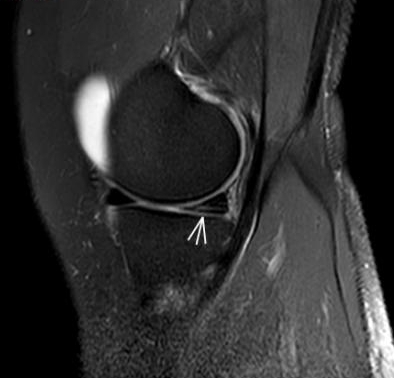

1. “咯吱響”+“卡頓感”——半月板的“碎玻璃警報”

場景:下蹲時膝蓋“咯噔”彈響,起身像被“卡住”

MRI偵查:精準(zhǔn)捕捉半月板撕裂或變性(半月板內(nèi)高信號),避免拖成“關(guān)節(jié)交鎖”

(半月板撕裂)